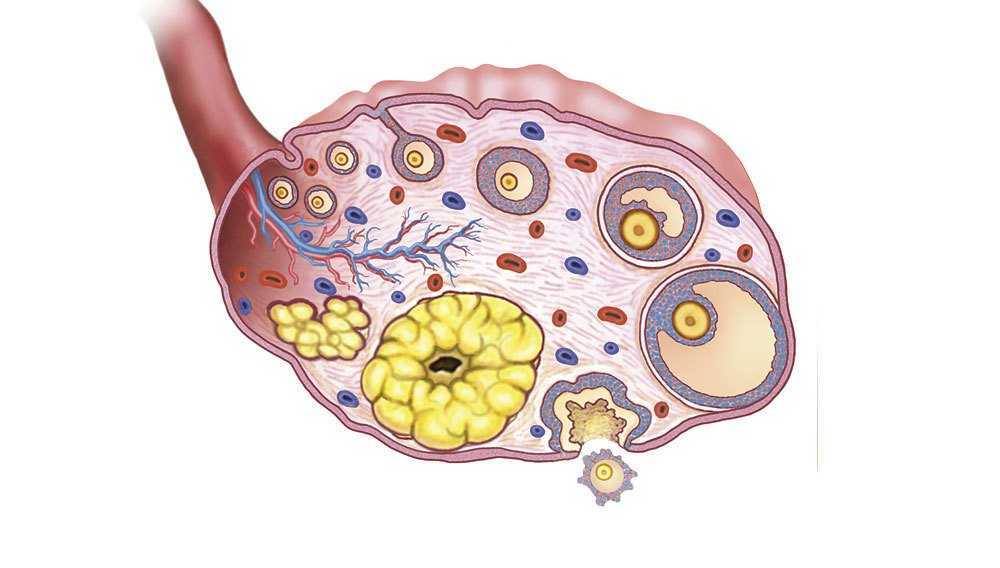

Созревание фолликула в яичнике: этапы и процессы